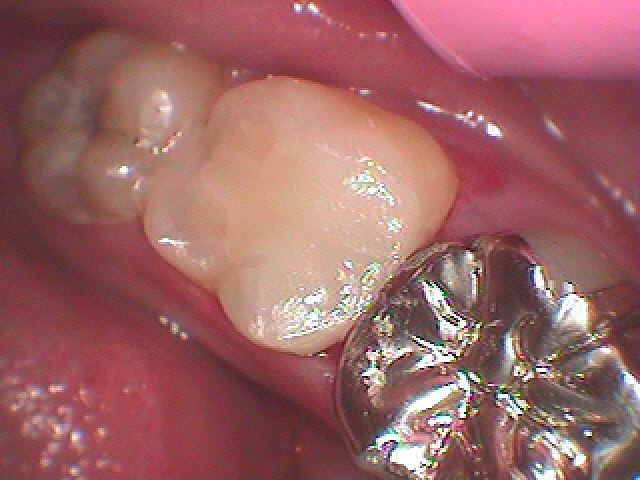

セレックセラミックにて修復しています

本来の歯のように綺麗に仕上がりました